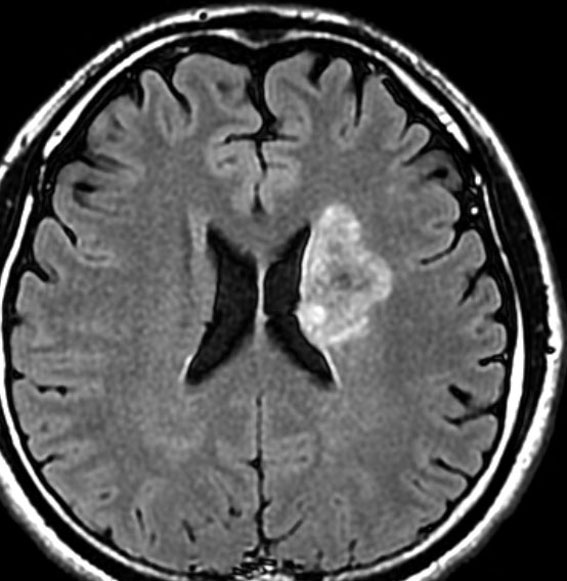

放射線治療後7週目

フレア画像です。腫瘍サイズが増大しています。もともと腫瘍周辺浮腫はなかったのですが大脳基底核と視床に浮腫が出現しています。スード・プログレッションの始まりです。